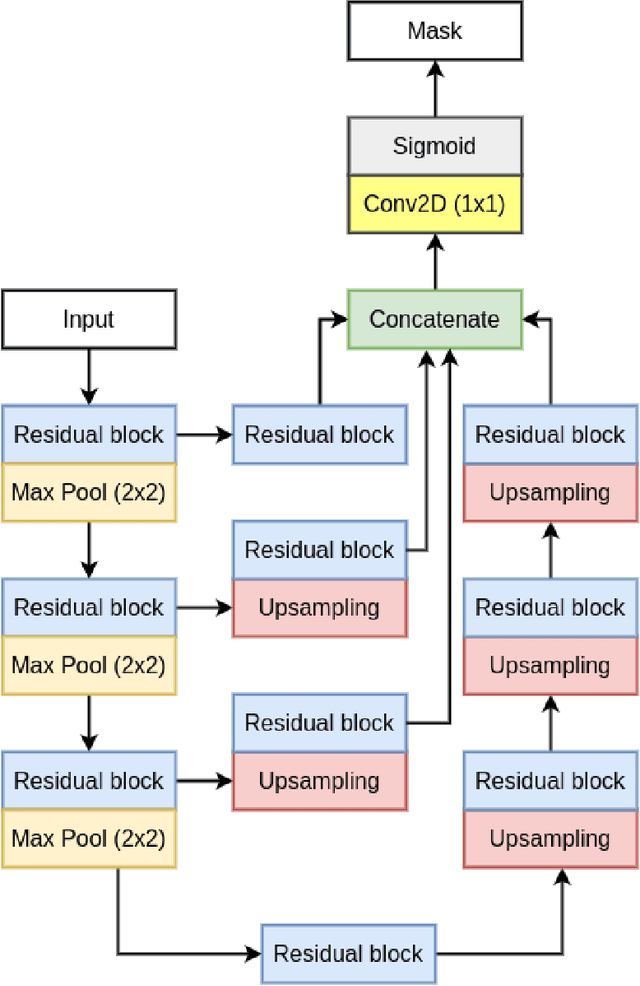

RUPNet: Residual upsampling network for real-time polyp segmentation

Colorectal cancer is among the most prevalent cause of cancer-related mortality worldwide. Detection and removal of polyps at an early stage can help reduce mortality and even help in spreading over adjacent organs. Early polyp detection could save the lives of millions of patients over the world as well as reduce the clinical burden. However, the detection polyp rate varies significantly among endoscopists. There is numerous deep learning-based method proposed, however, most of the studies improve accuracy. Here, we propose a novel architecture, Residual Upsampling Network (RUPNet) for colon polyp segmentation that can process in real-time and show high recall and precision. The proposed architecture, RUPNet, is an encoder-decoder network that consists of three encoders, three decoder blocks, and some additional upsampling blocks at the end of the network. With an image size of $512 \times 512$, the proposed method achieves an excellent real-time operation speed of 152.60 frames per second with an average dice coefficient of 0.7658, mean intersection of union of 0.6553, sensitivity of 0.8049, precision of 0.7995, and F2-score of 0.9361. The results suggest that RUPNet can give real-time feedback while retaining high accuracy indicating a good benchmark for early polyp detection.